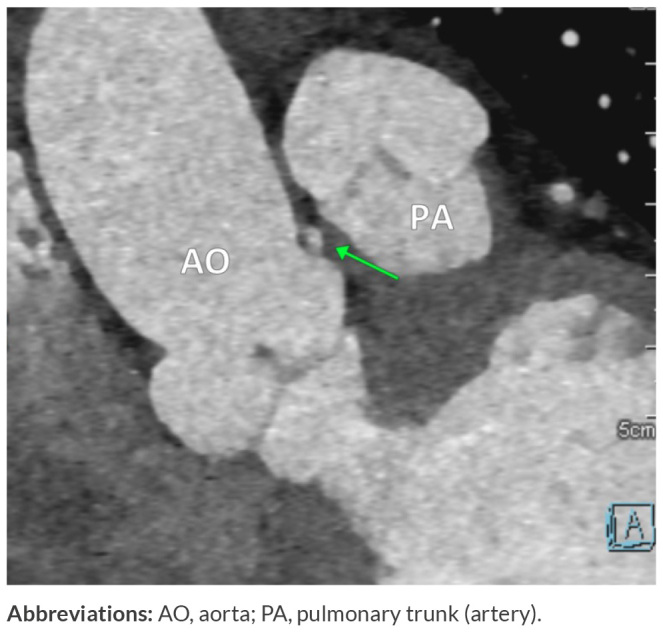

冠状动脉起源异常是一种罕见的先天性疾病,可表现为非特异性胸痛或呼吸短促或无症状。早期识别是至关重要的,因为某些变异与心脏性猝死的高风险有关。在此,我们报告一例53岁女性高血压,甲状腺功能减退,肥胖(II级)和间歇性胸痛放射到左臂两年的病史。心脏科检查包括心电图、心脏酶、超声心动图和CT冠状动脉造影显示右冠状动脉(RCA)起源于左冠状动脉主干(LMCA),但血流动力学上没有明显的狭窄。本病例强调了先进成像技术在评估非典型胸痛中的重要性,它可以揭示冠状动脉的关键先天性异常。虽然该异常与本例患者的缺血无关,但其识别对于适当的管理和风险分层至关重要。学习要点:先进的成像技术在评估非典型胸痛时很重要,它可以显示冠状动脉的关键先天性异常。CT冠状动脉造影仍然是诊断和风险评估的重要工具。尽管本例中右冠状动脉与缺血无关,但持续监测和心血管危险因素管理对于长期预后至关重要。

Anomalous origin of the coronary arteries is a rare congenital condition that can present as non-specific chest pain or shortness of breath or remain asymptomatic. Early identification is critical as certain variants are linked with a high risk of sudden cardiac death. Here, we report the case of a 53-year-old female with hypertension, hypothyroidism, obesity (class II) and a history of intermittent chest pain radiating to the left arm for two years. A cardiology workup including ECG, cardiac enzymes, echocardiography and CT coronary angiography revealed an anomalous origin of the right coronary artery (RCA) arising from the left main coronary artery (LMCA) with no haemodynamically significant narrowing. This case highlights the significance of advanced imaging techniques in evaluating atypical chest pain, which can reveal critical congenital anomalies of the coronary arteries. Although this anomaly was not associated with ischaemia in our patient, its recognition is vital for appropriate management and risk stratification.

Learning points: Advanced imaging techniques are important in evaluating atypical chest pain, which can reveal critical congenital anomalies of the coronary arteries.CT coronary angiography remains an essential tool for diagnosis and risk assessment.Although the right coronary artery was not associated with ischaemia in this case, continued monitoring and cardiovascular risk factor management are essential for long-term prognosis.